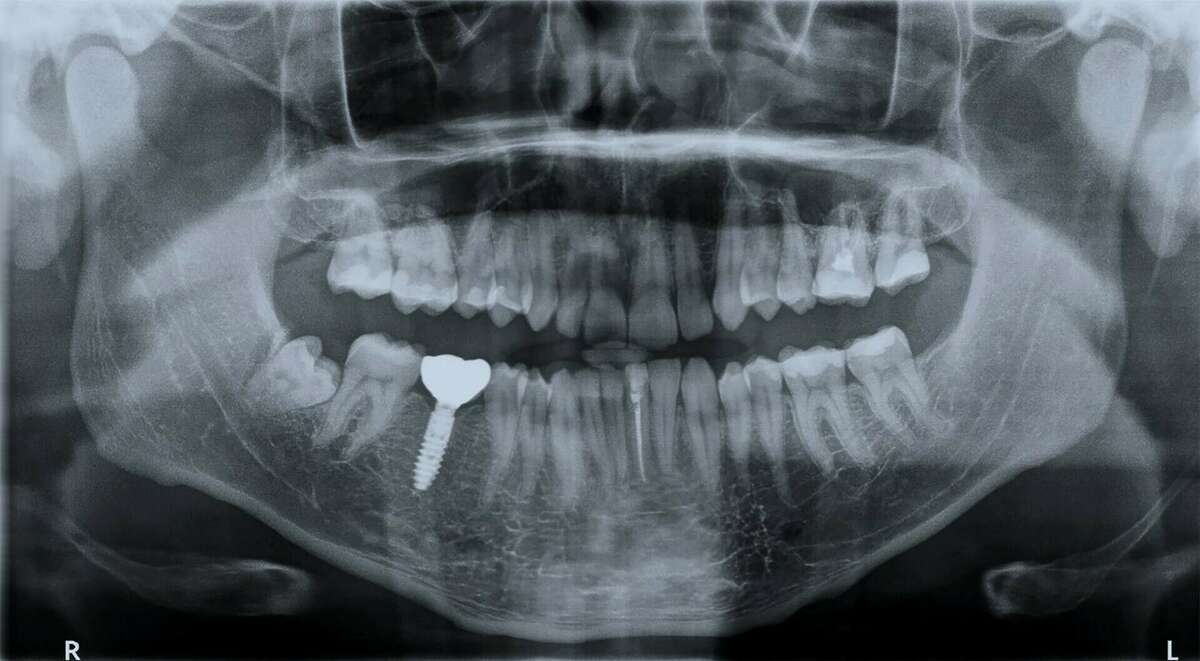

La technique Flapless

Les avantages de la technique Flapless sont bien connus et nous assistons à une évolution de ce paradigme avec les nouvelles générations de trépans muqueux.

Une méthode qui présente de nombreux avantages : une intervention moins longue tant pour le patient que pour le praticien et un plateau technique réduit.

Les suites postopératoires sont moins douloureuses et œdémateuses, entraînant moins de gênes pour le patient. La prise d’antalgique de première intention est réduite, voire parfois inutile dans certains cas

Le chirurgien-dentiste doit être formé et apte à pratiquer la technique, prévenu et conscient de la précision demandée. Les examens préopératoires pour évaluer la quantité du volume osseux et gingival ainsi que l'analyse des images en tomographie numérique d’une grande qualité et précision sont indispensables.